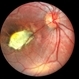

- central disciform scar

- Fundus photograph and OCT scan of an 86-year-old man with long-standing type I diabetic proliferative retinopathy.